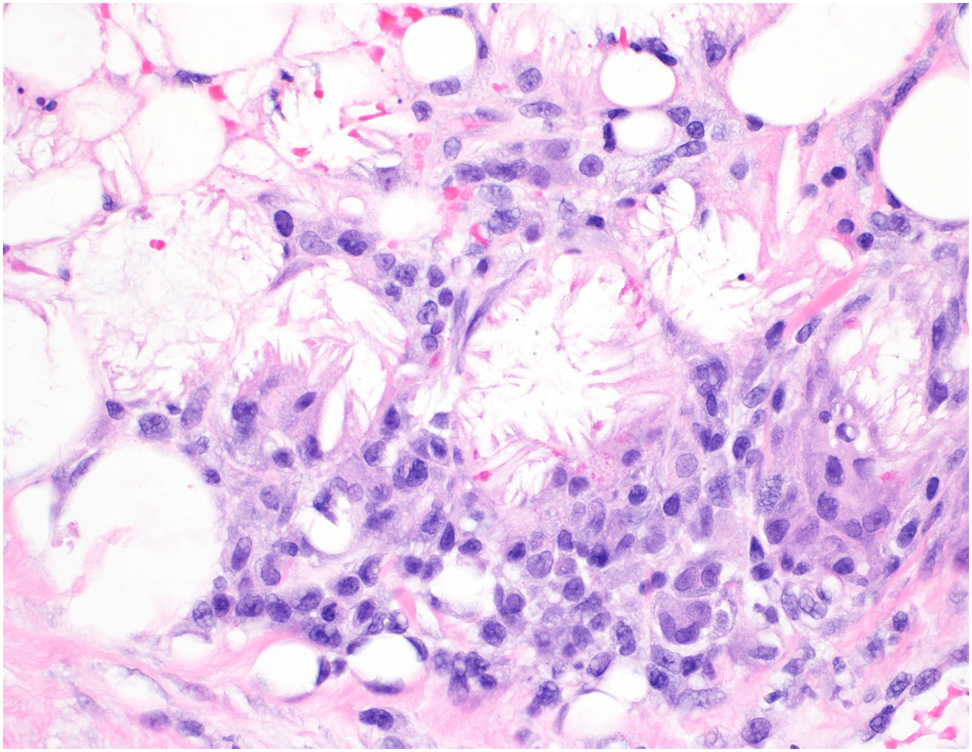

On day 12, dermatology was consulted again to examine a scaly eruption of unknown etiology over the affected areas which was managed with hydrocortisone 2.5% cream and hydrophilic topicals (Figure 3). A punch biopsy was obtained, which confirmed subcutaneous fat necrosis with crystals and focal lymphohistiocytic inflammation (Figure 4). Dermatology again recommended daily calcium monitoring with pediatric endocrinology follow up. His serum calcium was next checked on day 14 and 17, both levels were elevated at 11.9 and 13.2 mg/dL, respectively (normal 8.8–11.3 mg/dL) [7]. His ionized calcium was also elevated to 1.64 mmol/L at this time, but serum magnesium, phosphorous, alkaline phosphatase, and albumin were within normal limits. Throughout this time, the patient did have symptoms of hypercalcemia, as he was exhibiting feeding intolerance due to signs of gastrointestinal reflux and immature oromotor skills requiring partial gavage. On day 17, pediatric endocrinology was consulted for hypercalcemia; he was treated with furosemide and switched to a low calcium formula. His platelet count normalized on day 18. His serum calcium levels were monitored every 12 h and peaked at 13.9 mg/dL on day 20. A 2 mg/kg per day dose of oral prednisolone was added to his treatment regimen for two months, then decreased to 0.4 mg/kg for two weeks before discontinuing.

Histology of the left hip revealed subcutaneous fat necrosis with crystals and focal lymphohistiocytic inflammation.